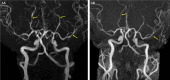

Figure 1. Magnetic resonance angiogram.

(A) Maximum intensity reconstruction from time of flight magnetic resonance angiogram (MRA) showing segmental irregularity and narrowing involving the distal bilateral posterior cerebral arteries and left middle cerebral artery (arrows). (B) Follow-up MRA after six weeks shows complete resolution of the vascular abnormality.